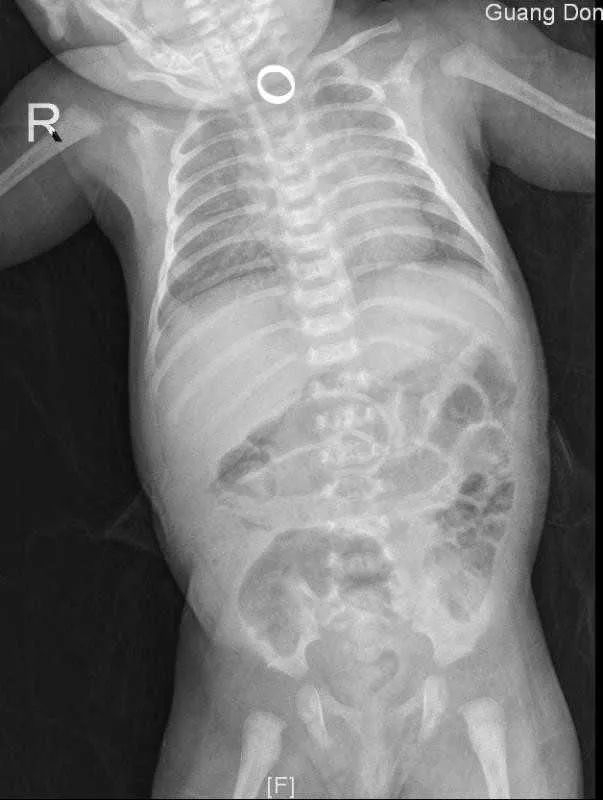

2月26日晚,广东茂名1月龄大的女婴可可(化名),在满月当天,家人按当地传统习俗给她戴上了5个代表吉祥如意美好祝福的黄金戒指,可一个不小心,在拉着孩子的手逗玩时,其中一枚戒指恰巧就掉进了小可可的嘴巴,并被吞了进去!家长们赶紧将可可倒立、拍背、扣喉……

使出浑身解数,但依旧无济于事,只能急急忙忙地将可可送到附近的医院,X线检查显示戒指位于食管上段,当地医院在尝试了各种方法后,仍是没有成功地将卡在可可食管里的戒指取出。

转到省妇幼儿童消化专科后,考虑患儿月龄尚小,食管黏膜薄嫩,管腔相对较窄,异物嵌顿后易造成消化道溃疡、穿孔、出血等风险,医生赶紧开辟急诊手术绿色通道,联合麻醉科、消化内镜中心等进行多科协作,为可可行超细胃镜下食管异物取出术。在麻醉科及消化内镜室护理团队的默契配合下,仅用10秒,医生就成功“拆除”了可可食管里的“定时炸弹”!

取出金戒指后,医生再次用超细胃镜细心地查看可可的食管情况,因为异物嵌顿,食管黏膜已经不可避免地出现损伤,但万幸的是还没有造成穿孔、大出血等严重后果。家长们悬着的一颗心,也终于可以放下来了。